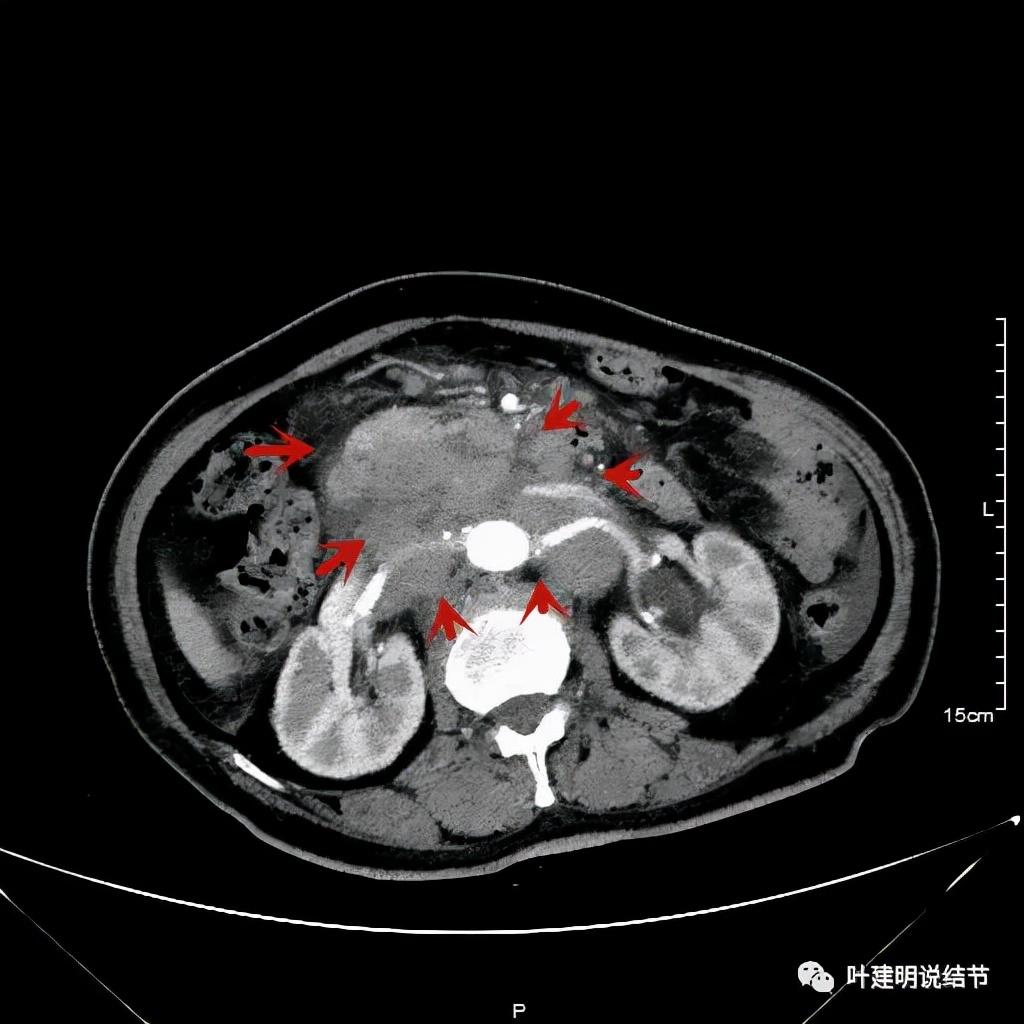

其实胸部CT示食管的病变感觉并不厉害,外侵或纵隔内转移均不明显,但其腹部的CT让人大吃一惊!

上图是初发现时的CT影像报告,其他CT图像上红色箭头所指范围内都是肿瘤,整合成团,挤压血管以及正常器官结构。你有见过原发灶这么不显眼,而腹部转移灶这么厉害的食管癌吗?但经过穿刺证实是转移性鳞癌,结合病史考虑是食管癌转移。手术自然是不可能了根治了,放疗也不合适,经过MDT并与患方充分沟通,依据食管癌治疗指南: